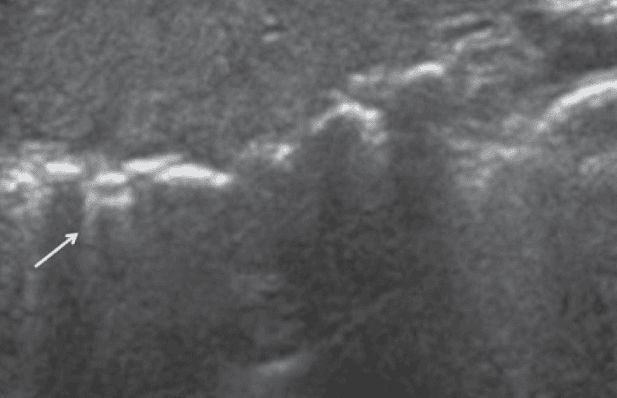

E lines are hyperechoic lines originating from air in the subcutaneous tissue that can sometimes be mistaken for B lines. One important feature of E lines is that they do not originate from the pleural line. Their presence may obscure adequate visualization of the pleural line.